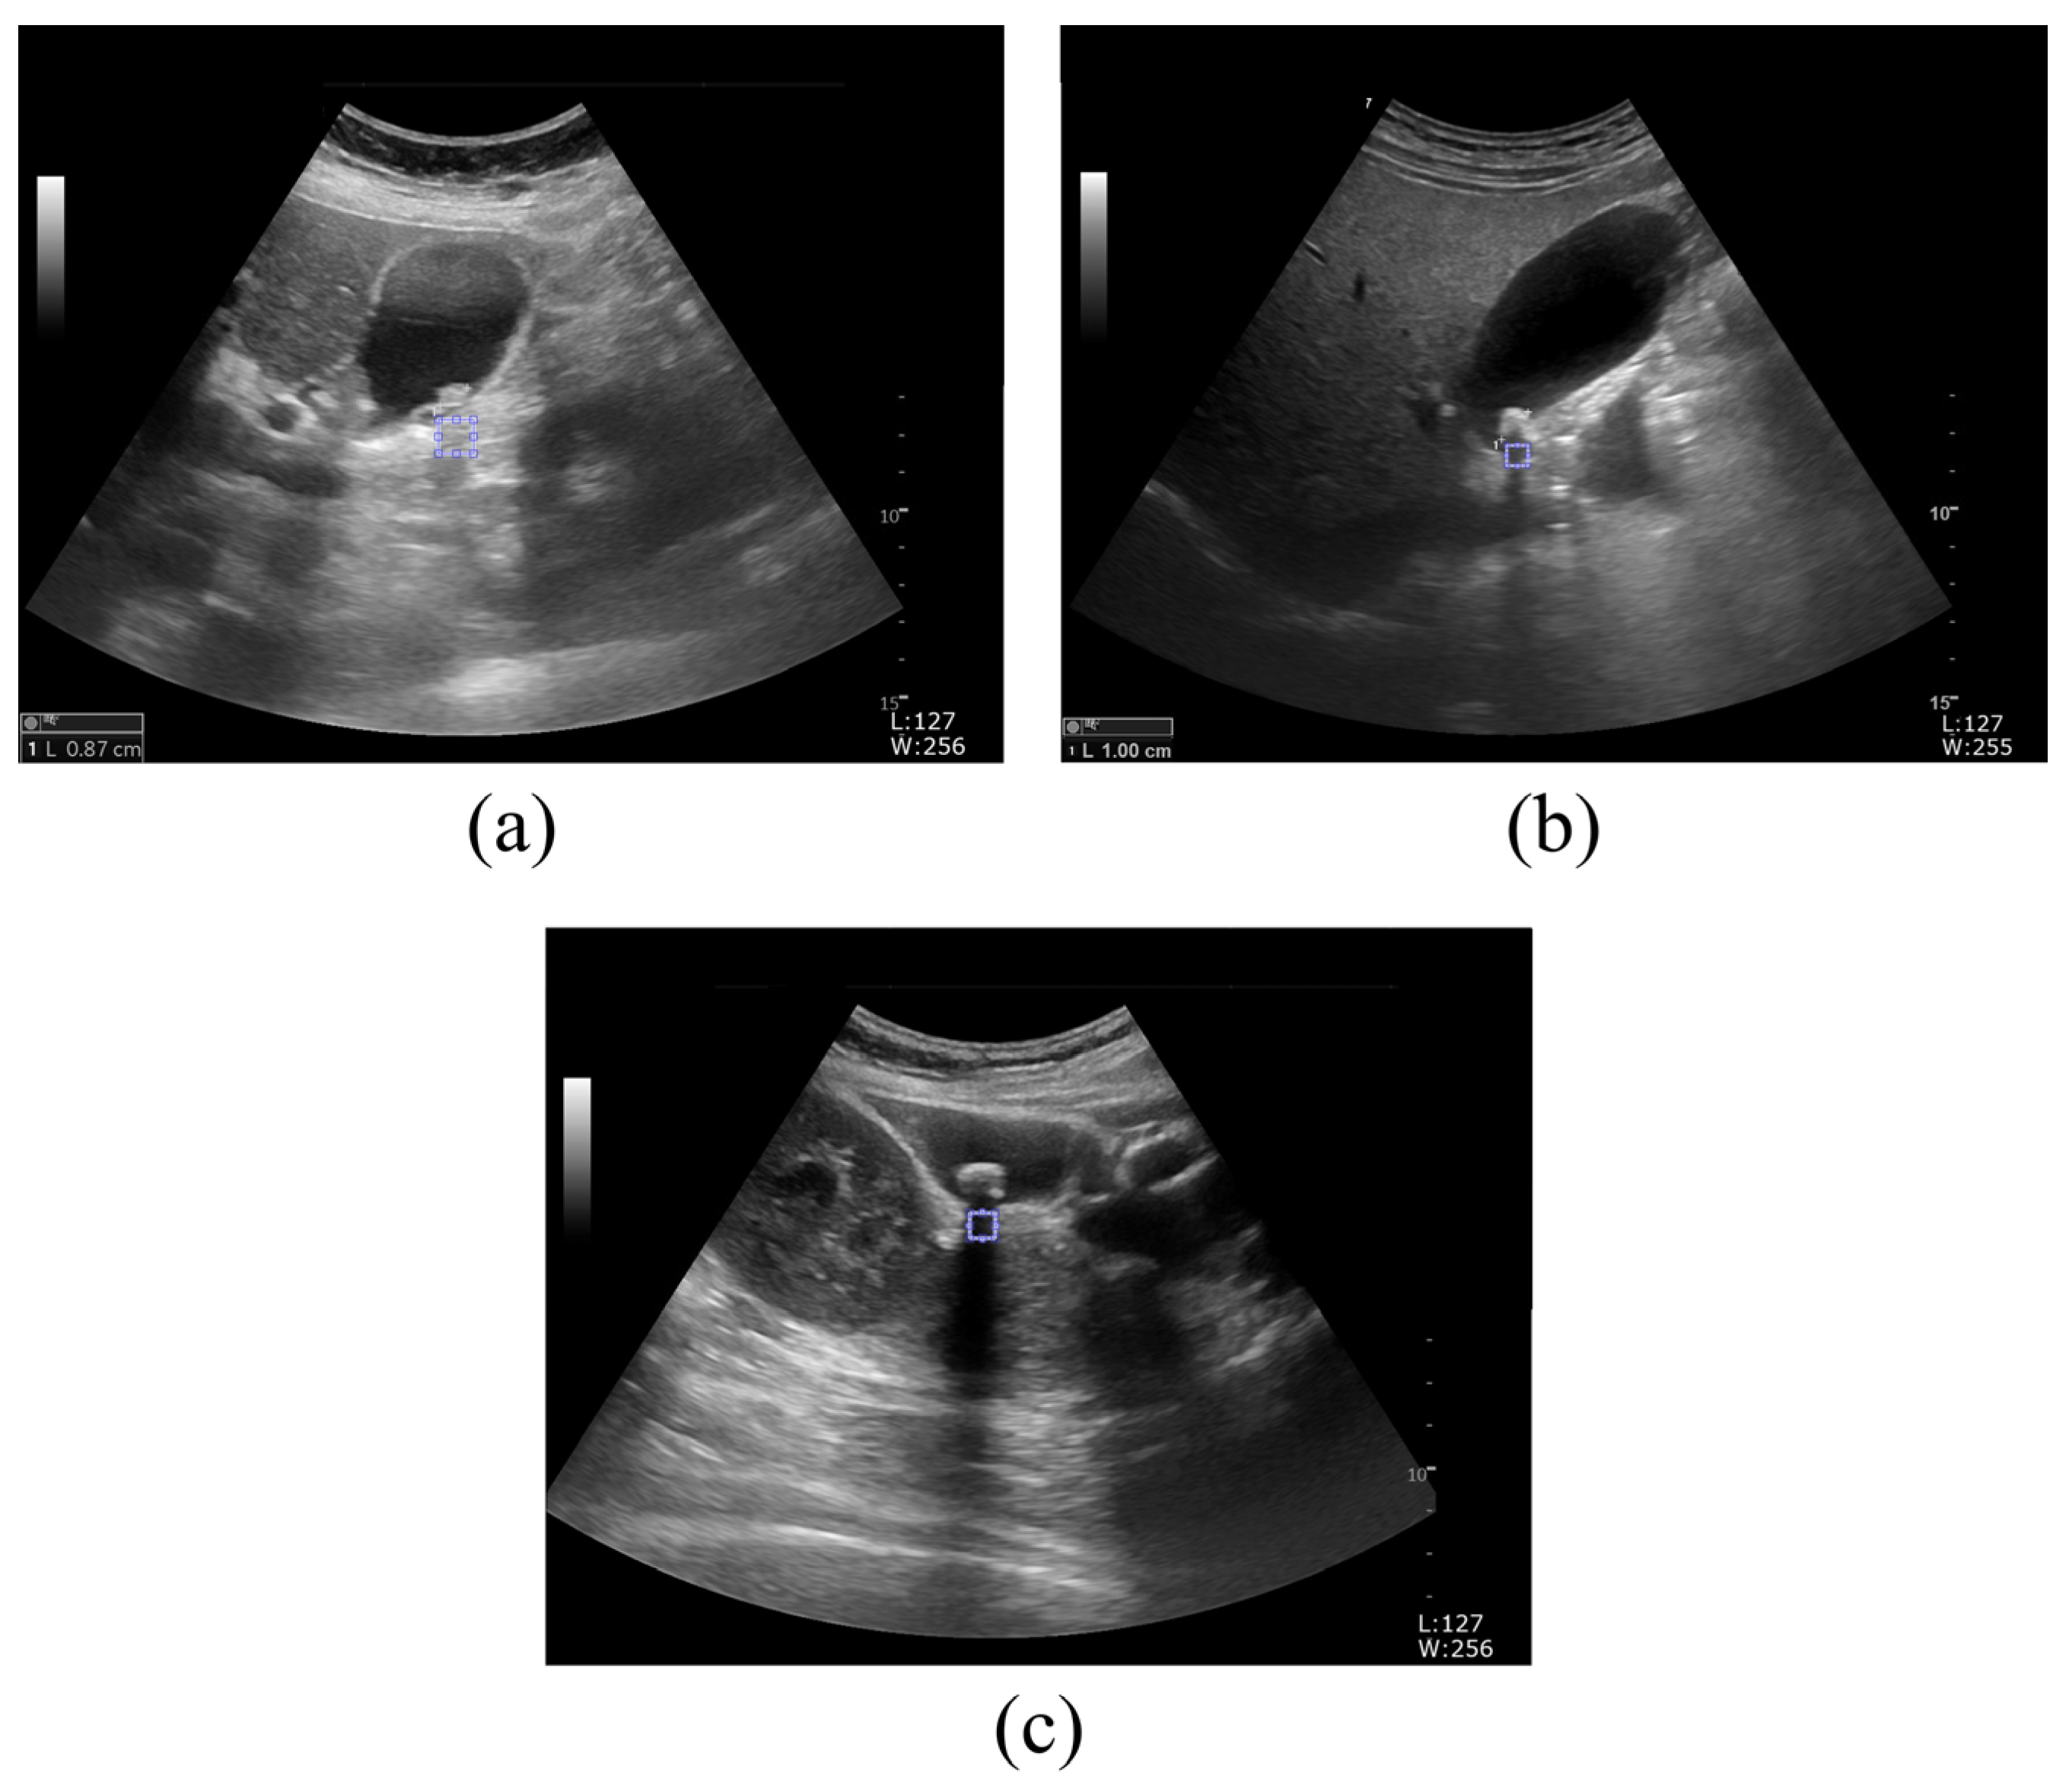

2.1. Ultrasound Image Acquisition

2.2. Proposed Framework to Determine Kidney and Gallbladder Stones Using the GLCM